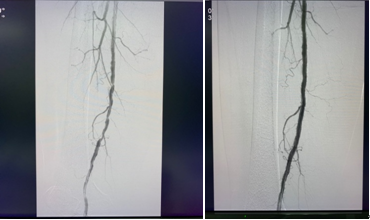

杨阿姨糖尿病多年,规律血液透析4年,下肢动脉硬化闭塞逐年加重,近期出现了一侧下肢的麻凉痛,无法行走,血管外科医生及时介入下球囊扩张后,疼痛明显缓解。目前由于疾病谱的改变,透析患者中合并糖尿病的患者越来越多,很多患者合并外周血管病变,包括糖尿病足等,严重的需要截肢。我们已经完成了多例患者下肢血管的球囊扩张及支架植入。

目前北京积水潭医院成立了血液透析血管通路小组,成员包括血透室护士、肾内科医师、血管外科医生及超声科医师。在当前形势之下,在严密的防护、避免院内感染的前提下,血管外科和肾内科联合积极有效的开展了血液透析通路相关的维护和治疗。包括自体、人工动静脉内瘘的建立,复杂导管置入及更换,自体动静脉内瘘取栓及PTA,人工血管取栓及PTA,中心静脉狭窄PTA术等。守护患者的生命线,我们在行动。